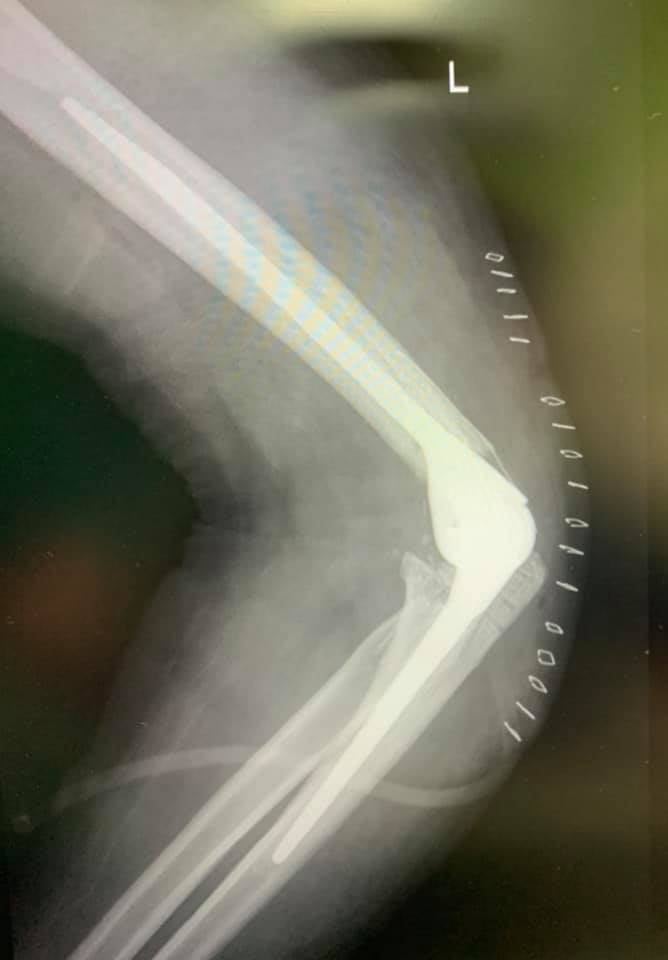

Гэмтэл Согог Судлалын Үндэсний Төвийн зөвлөх эмч, Монгол Улсын Хүний Гавьяат эмч Б.Бүргэдээр ахлуулсан Гар сарвуу нөхөн сэргээх бичил мэс заслын тасгийн баг хамт олон Монголд анх удаа “ТОХОЙНЫ ҮЕ БҮТЭН СОЛИХ” мэс заслыг амжилттай хийлээ. Тэргүүлэх зэргийн эмч Д.Даваажаргал, ахлах зэргийн эмч О.Цэрэндорж, мэдээгүйжүүлэгийн ахлах зэргийн эмч Д.Баярсайхан, сувилагч Д.Оюунцэцэг, мэс заслын сувилагч М.Амгаланпүрэв, Ц.Баттуяа, Б.Тамираа мэс заслын баг хамт олондоо ажлын амжилт хүсье.

Б.Бүргэд: Монголд анх удаа 20-н жилийн өмнө багштайгаа хамт мөрний үе солих мэс засал хийж нутагшуулж байлаа. Тус мэс засал нь өнөөдөр өдөр тутамд хийгддэг болсон. Тохойн үений бэртэл гэмтэл ихэссэн учир багийн нөхөдтэйгөө хамтарч Монголдоо анх удаа энэ төрлийн мэс заслыг маш амжилттай хийлээ. Цаашдаа энэ мэс заслыг нутагшуулах бололцоотой. Энэ мэс заслыг хийснээр Хөдөлмөрийн чадвар алдалтыг бүрэн зогсоож, тухайн хүний амьдралын чанар сайжрах боломжтой юм. Цаг ямагт шинэ содон зүйлийг нэвтрүүлж, ард иргэдийнхээ эрүүл мэндийн төлөө зүтгэж буй баг хамт олондоо талархал илэрхийлье.